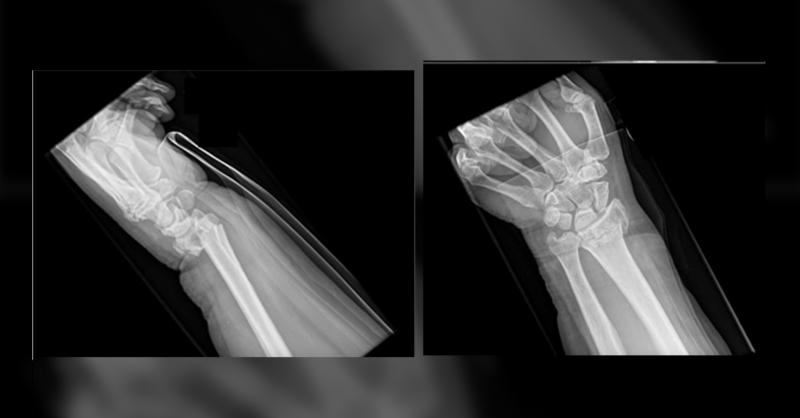

The Post-traumatic Radioulnar Synostosis in a 57 year old Man

Distal radius fracture is very commonly seen among adults. Many surgical modalities are available for fixing distal radius fractures, including external fixator, K-wires percutaneous fixation, bridging plate, and open reduction and internal fixation(ORIF). However, there are multiple complications reported subsequent to non-operative or operative t